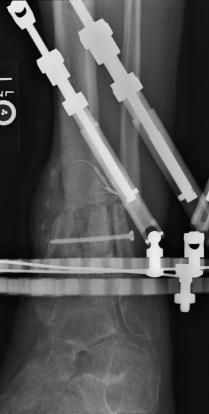

Postoperative (13th) images of left ankle

The image(s) displayed here were created following Liam's 13th surgery which was performed by Dr. Saunders. After a few hiccups getting

the surgery scheduled, Liam spent most of the September 13th afternoon in his 13th surgery. ;-) The surgery lasted about 5 hours and according

to the doctor, it was a good surgery. The 1st photo shows the new frame bracing that holds Liam's ankle together. The next series of photos show

various angles of the ankle and the rods that go from the frame into and through the left ankle. There was some concern that the swelling would

burst and allow for infection. Looks like we are now past that concern. Liam is still on antibiotics to ward of potential infection. The flesh

images show how the skin reacts to having the leg adjusted by the brace. The doctor has had to cut the skin to allow the rods to move freely.